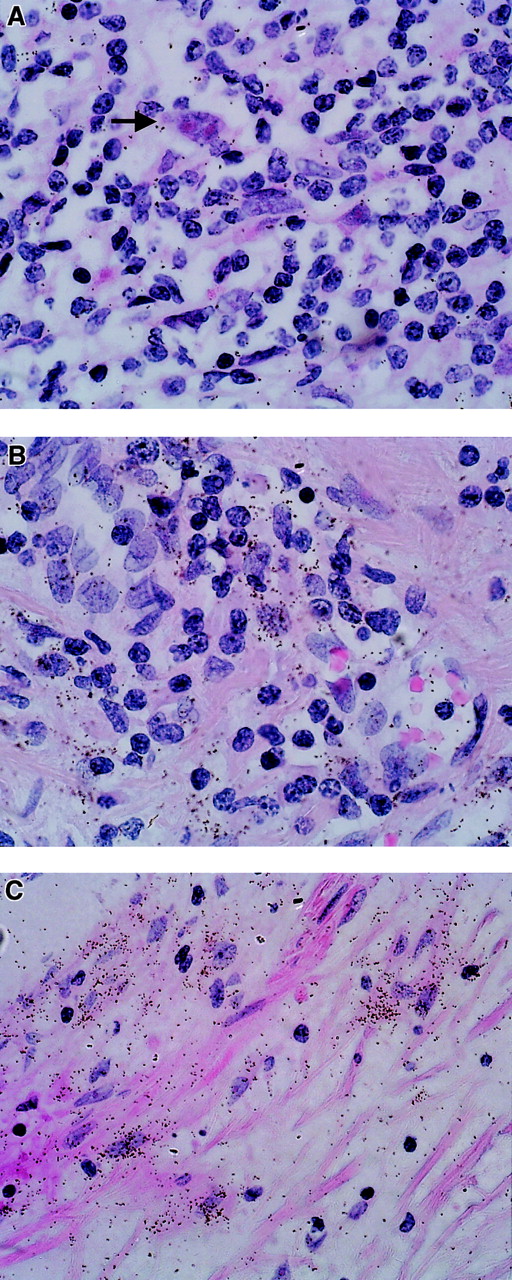

In a set of experiments using paraffin-embedded lymph node tissue sections from 8 patients with the NS subtype of HD and 7 patients with the MC subtype, we conducted assays for RNA expression of TIMP-1. TIMP-1 expression was detected in the samples from 14 of the 15 patients; in one additional sample, expression at the lowest detection limit was observed (Figure 1A and B and Figure 2). In every sample in which expression was observed, the H/R-S cells showed expression of TIMP-1. However, among these cases, various percentages—between 3% and 80%—of H/R-S cells were positive (Figure 2). Although there was a trend toward a higher percentage of H/R-S cells expressing TIMP-1 in samples from patients with the MC subtype, there was no significant difference in TIMP-1 expression between the NS and MS histological subtypes (Figure 2). Distinct, though light, positive signals were also detected in reactive lymphoid tissue distributed throughout the lymph nodes from all patients (both HD subtypes; Figure 1). These signals were most pronounced in areas of active tissue remodeling (Figure1C).

TIMP-1 expression (ISH analysis) in sections of lymph nodes from patients with HD.

Positive cells are characterized by an accumulation of black or brown stains (arrows). (A,B) TIMP-1 expression in H/R-S cells, and TIMP-1 expression in reactive lymphoid tissue. (C) TIMP-1 expression in areas of tissue remodeling.

Weak expression of TIMP-2 RNA was observed in all samples examined. In contrast to the results for TIMP-1, H/R-S cells were negative for TIMP-2 RNA (Figure 3A). On the other hand, reactive lymphoid tissue showed faint expression of TIMP-2 in some areas of tissue remodeling (Figure 3B). There was clear expression in fibrotic areas and lymph node capsules (Figure3C).

TIMP-2 expression (ISH analysis) in sections of lymph nodes from patients with HD.

Positive cells are characterized by an accumulation of black stains. (A) TIMP-2–negative H/R-S cells (arrow). (B) TIMP-2 expression in reactive lymphoid tissue. (C) TIMP-2 expression in fibrotic areas.